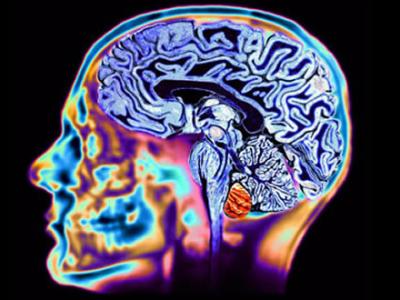

科学家称现代科学技术威胁人类大脑

科学家研究认为,现代科学技术对人类大脑的影响已成为当今人类面临的最大威胁之一...

散步能够让大脑保持年轻

散步能够让大脑保持年轻 散步可以强身健体,使身体变得灵活...